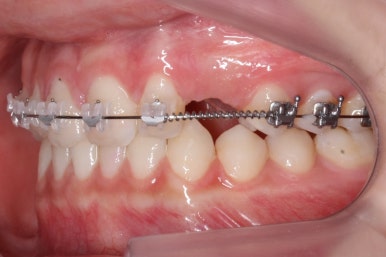

부산매복치아교정 키다리아저씨치과에서 소수술을 마친 모습입니다.

우선 남아있던 유치는 발치를 했고, 매복 송곳니에 장치를 붙인 후 잇몸 밖으로 체인 형식의 연장선만 빼놓았습니다. (두 개의 화살표 중 위쪽 화살표) 매복치아를 적절한 방향으로 요리조리 당겨줘야 하기 때문에 미니스크류를 이용했습니다. (두 개의 화살표 중 아래쪽 화살표)

수평으로 누워있었던 송곳니의 각도가 바로 잡힐 때까지는 계속 미니스크류만을 이용해서 당겨줍니다. 치아는 뼈속에서 헤엄치듯이 조금씩 방향을 잡아갑니다.